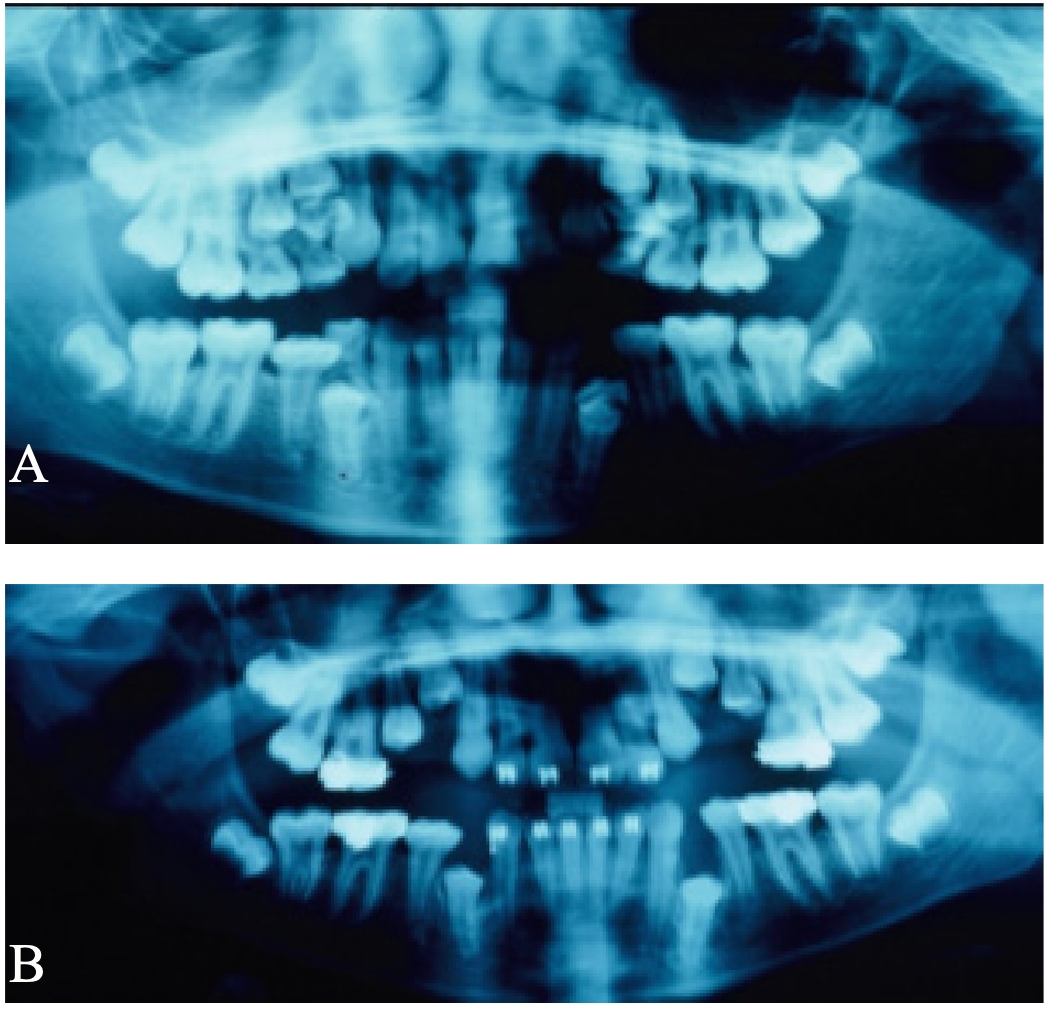

Caso 3. Paciente masculino de 15 años quien acude a consulta por falta de espacio en los maxilares. Los padres firmaron consentimiento informado. No refieren tratamiento de ortodoncia u ortopedia previo. Paciente con antecedentesdealergiaalosácaros,intervención quirúrgica de amígdalas y adenoides a los 7 años, con múltiples tratamientos por sinusitis. Alcanzó el desarrollo puberal a los 14 años y medio. Padre y madre tuvieron tratamiento de ortodoncia por apiñamientos y discrepancias estéticas. Al momento del examen diagnóstico presentó maloclusión Clase I con mordida profunda anterior, retención prolongada de los segundos molares inferiores primarios derecho e izquierdo debajo del plano oclusal inferior y debajo del plano oclusal inferior, con impactación de segundos premolares inferiores derecho e izquierdo. Además los incisivos laterales superiores se observan estrechos mesio-distalmente (Figura 3). El tratamiento consistió en: remoción del segundo molar primario inferior izquierdo y derecho retenido, terapia ortodóncica con aparatología fija .022 de Straightwire en ambos arcos dentarios.

Figura 3. Radiografía panorámica y periapicales iniciales, mostrando los segundos molares primarios retenidos en infraoclusión y la impactación de los segundos premolares inferiores.

El hermano mayor presentó canino superior izquierdo impactado. Los padres firmaron consentimiento informado. Al momento de la consulta el paciente presentó como diagnóstico: clase II con protrusión dentaria antero-superior, con ambos primeros molares superior e inferior izquierdo con un retraso importante de su erupción de 4 años. Además en la radiografía panorámica se observó impactación de canino superior derecho y de los dos premolares inferiores izquierdos. También presentó pérdida prematura del segundo molar inferior derecho primario por caries, el cual fue extraido sin colocar apropiado mantenedor de espacio, trayendo como consecuencia migración mesial del primer molar inferior izquierdo, agravando falta de espacio para la normal erupción de los premolares inferiores izquierdos. (Figura 5). El tratamiento consistió en: exposición quirúrgica del primer molar permanente superior e inferior izquierdo, terapia ortodóncica con expansión palatina rápida y aparato extra-oral de tracción cervical, combinado con ortodoncia correctiva con aparatología fija .022 de Straightwire.

Figura 5: Radiografías panorámica inicial y dos radiografías panorámicas de progreso, donde se evidencia la impactación de los primeros molares superiores e inferiores, la inclinacion mesial del primer molar inferior izquierdo asociada a la pérdida prematura del segundo molar primario inferior izquierdo, produciendo impactación a su vez de los premolares inferiores izquierdos.

Figura 6: Radiografía panorámica inicial (A) y radiografía panorámica de progreso (B), luego de extracción de los molares primarios retenidos y molares primarios supernumerarios.